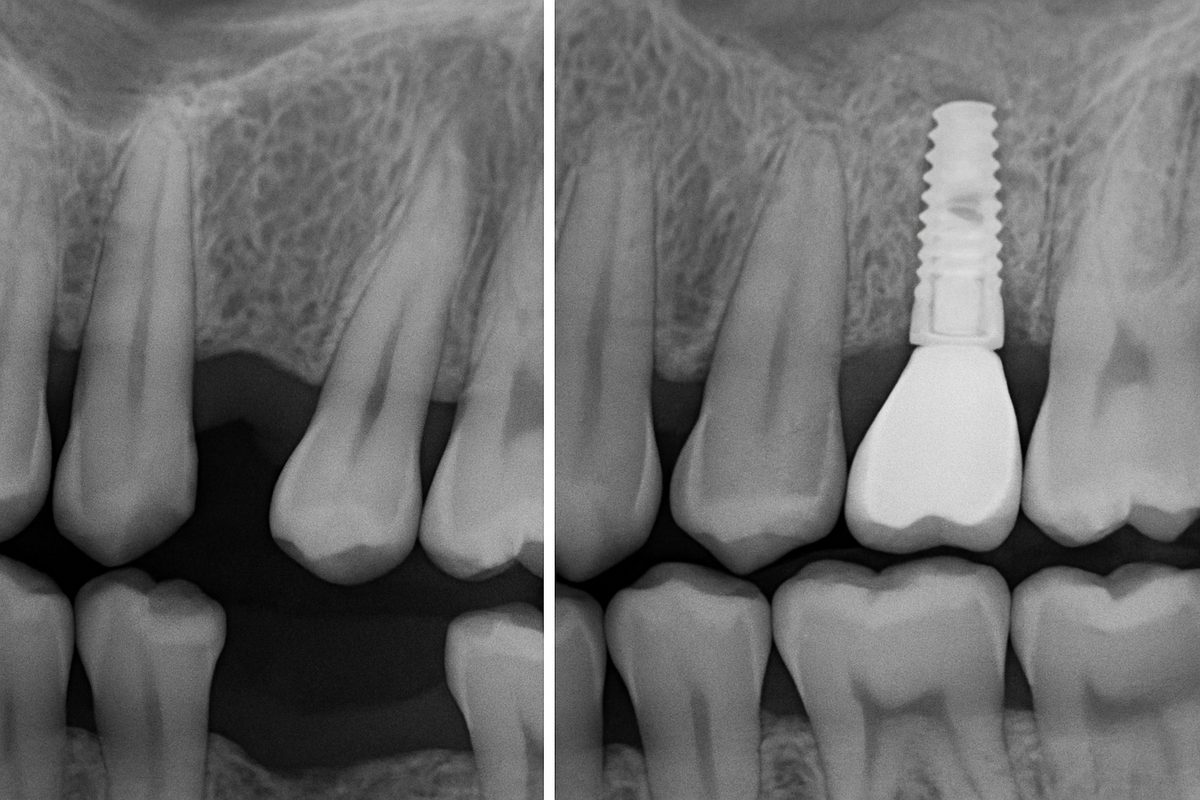

Consultation & 3D Imaging

The process starts with an exam, digital x-rays, and often a CBCT scan to map bone and nerves. This planning helps the team choose implant size, angle, and whether bone grafting is needed. Clear images reduce surprises during surgery and improve outcomes.

Surgery: Placing the Implant

Surgery is usually done with local anesthesia and optional sedation. The surgeon drills a small site in the jawbone and places the implant fixture. Many centers use guided or navigated surgery to increase precision and speed healing. The site is closed to begin the healing phase.

Osseointegration & Final Restoration

Over weeks to months the bone fuses to the implant in a process called osseointegration. Once stable, the abutment is attached and a custom crown, bridge, or denture is made and placed. Final restorations restore chewing, speech, and appearance.